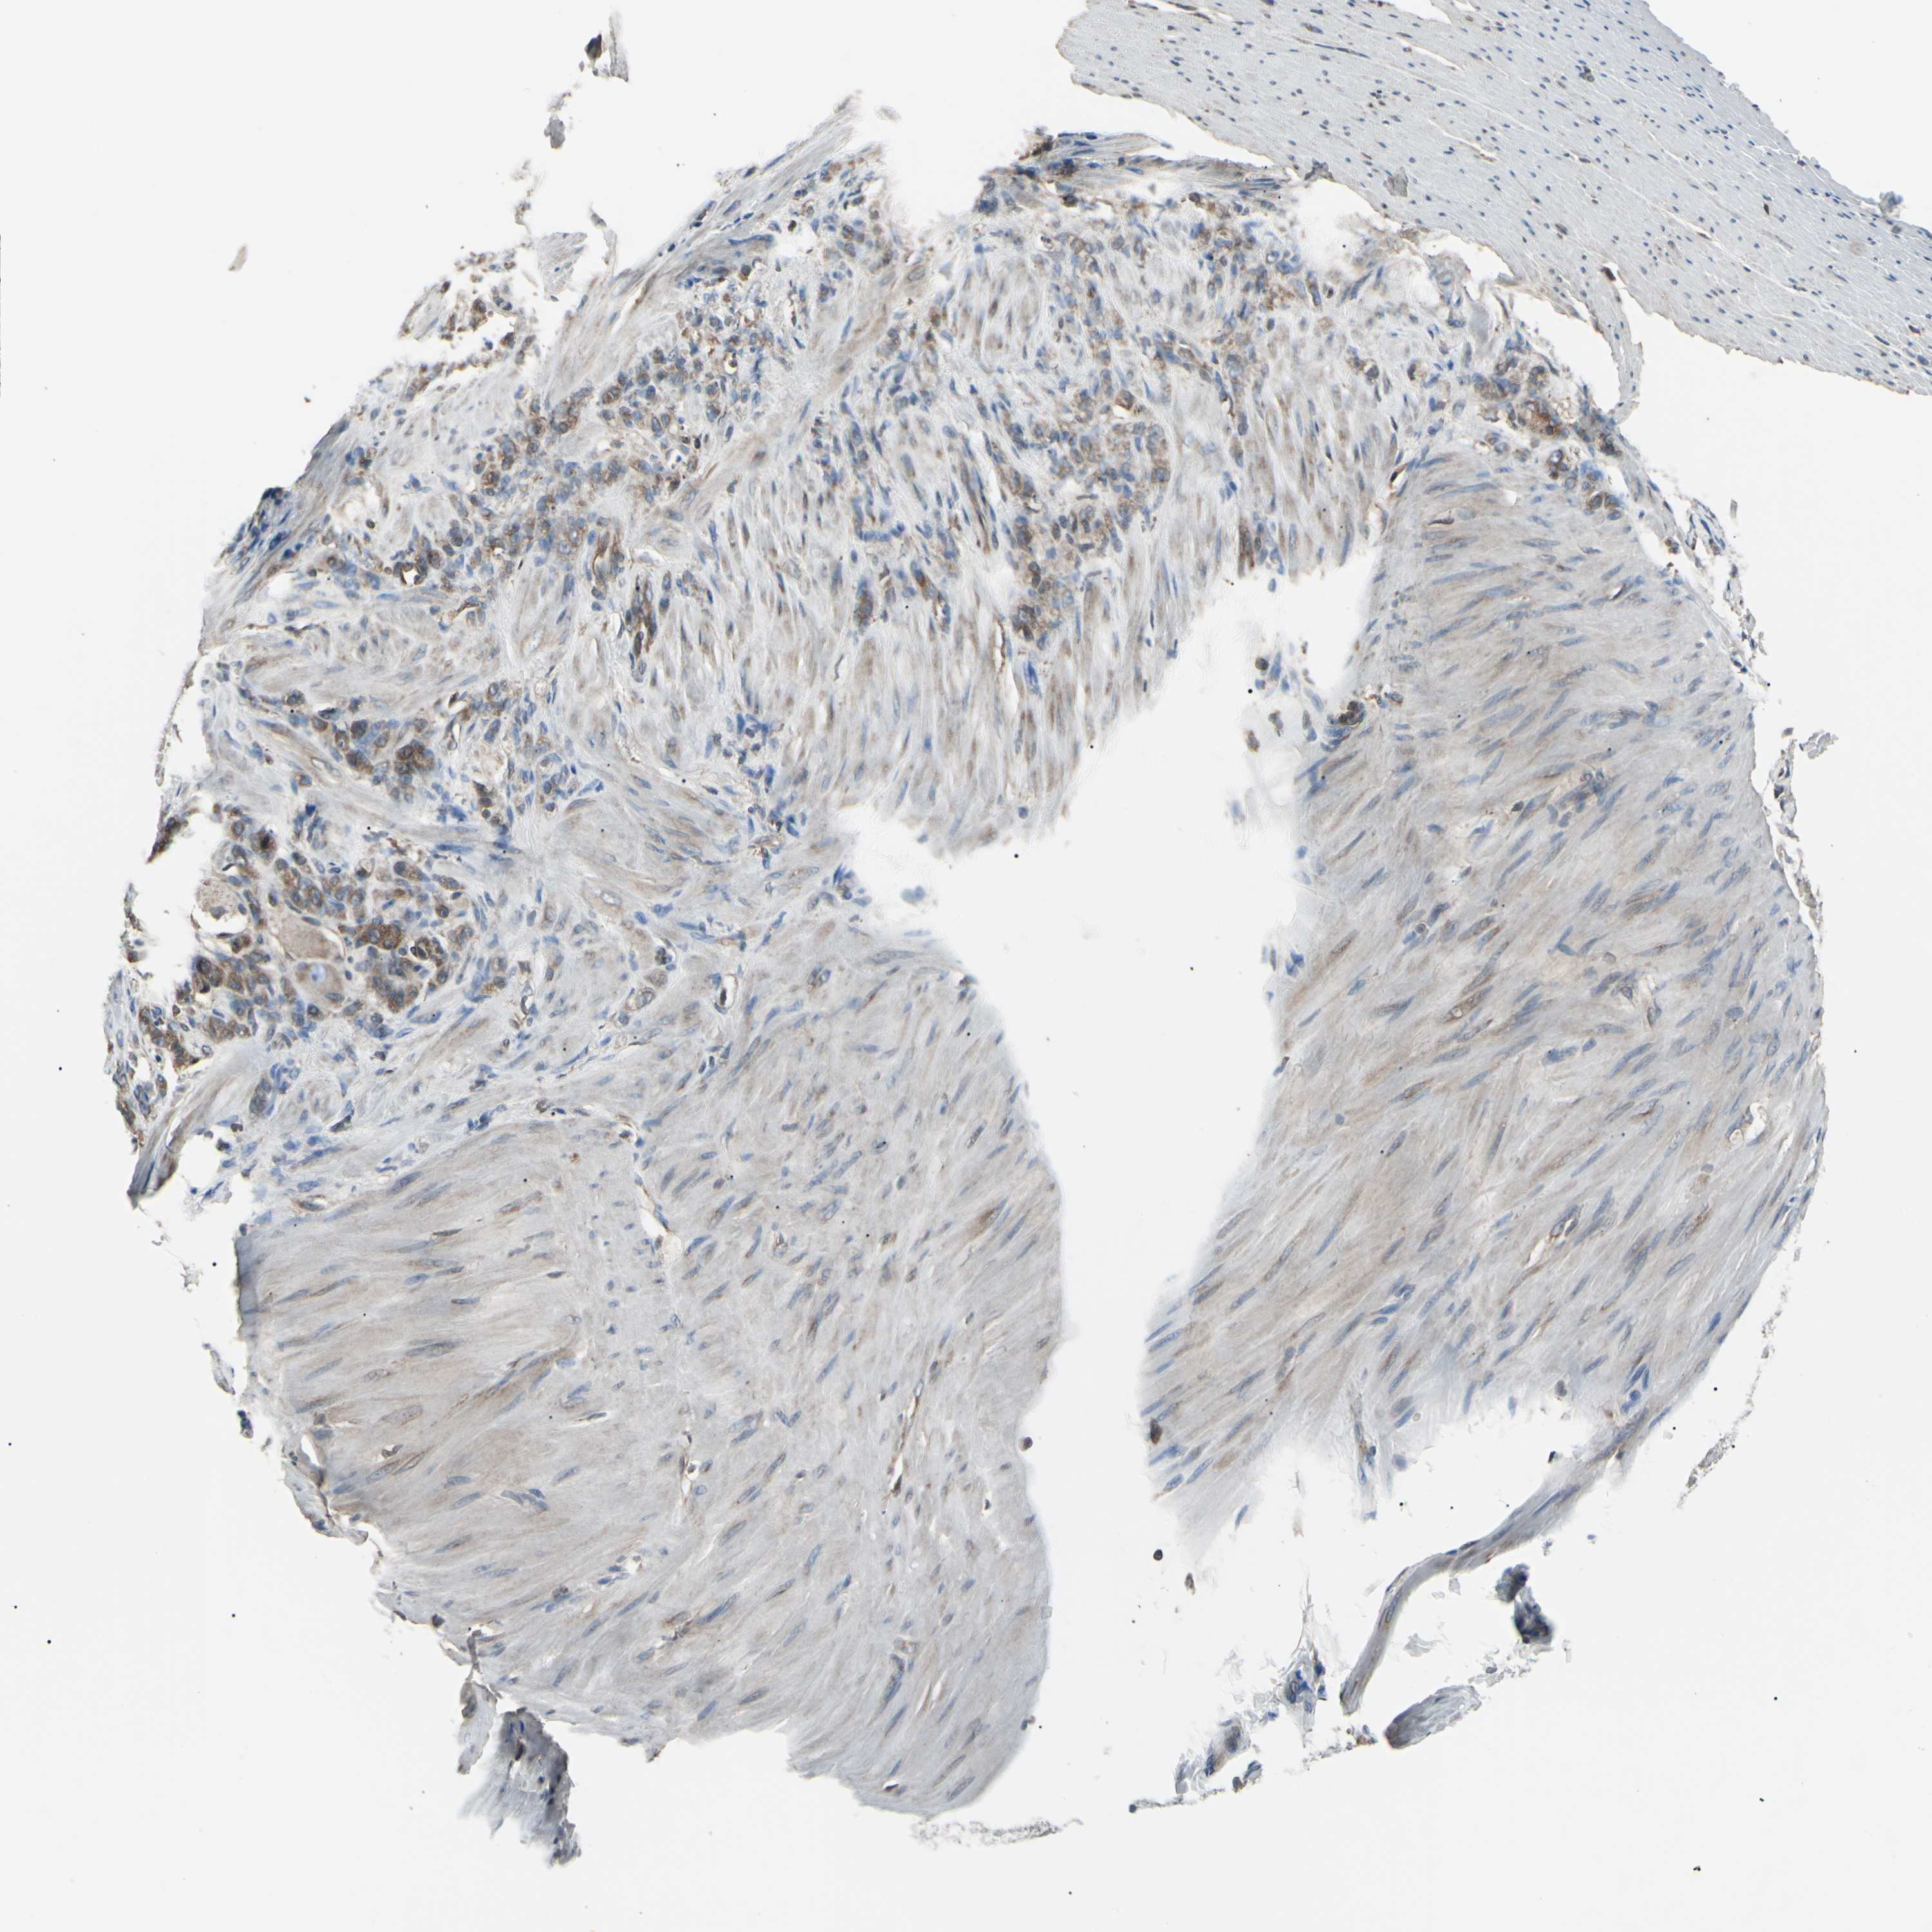

STOMACH CANCER - Protein expressioni

A mouse-over function shows sample information and annotation data. Click on an image to view it in a full screen mode. Samples can be filtered based on level of antibody staining by selecting one or several of the following categories: high, medium, low and not detected. The assay and annotation is described here.

Note that samples used for immunohistochemistry by the Human Protein Atlas do not correspond to samples in the TCGA dataset.

Antibody stainingi

Antibody staining in the annotated cell types in the current human tissue is reported as not detected, low, medium, or high, based on conventional immunohistochemistry profiling in selected tissues. This score is based on the combination of the staining intensity and fraction of stained cells.

Each image is clickable and will lead to virtual microscopy that enables deeper exploration of all samples and also displays staining intensity scores, fraction scores and subcellular localization as well as patient and tissue information for each sample.

Antibody HPA003600

Antibody CAB009337

Staining

High

Medium

Low

Not detected

Intensity

Strong

Moderate

Weak

Negative

Quantity

>75%

75%-25%

<25%

None

Location

Nuclear

Cytoplasmic/membranous

Cytoplasmic/membranous,nuclear

Adenocarcinoma, NOS

Adenocarcinoma, High grade